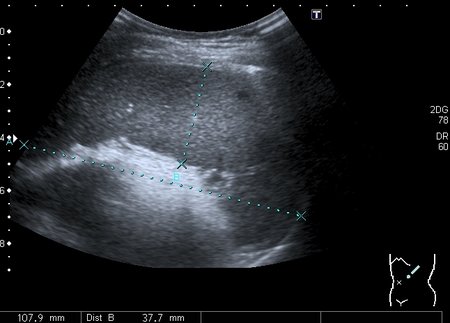

Девочка 13 лет, в течение 2-х недель температура до 38, СОЭ - 40 мм\ч, СРБ - 30.

На УЗИ: Учитывая клинику, лабораторные данные поставил гистиоцитарную инфильтрацию печени и селезёнки при генерализованной инфекции. Несколько раз встречался со схожими случаями, на фоне антибиотикотерапии изменения уходили. Но в данном случае девочка уже получала антибиотики в течение недели, на этом фоне не получено ни клинического , ни лабораторного улучшения, а на УЗИ очаги стали больше. Нужно ли расширять дифференциально -диагностический ряд? Ваши мнения

Имхо, по УЗ-семиотике - множественные небольшие абсцессы.

Мне нравится информация по данной патологии из видаровского "Клинического руководства по ультразвуковой диагностике в педатрии". Там данные изменения носят название очаговых поражений инфекционной этиологии (иерсиниоз, псевдотуберкулёз, токсокароз, хламидиоз и др.). Но инфекционисты, проведя ИФА с очень скудным набором диагностикумов и получив отрицательный результат, так же говорят, что это "не их".

Есть мысль о КТ с контрастированием , думаю в данных очагах накопление контраста должно отличаться от очаговых поражениях при лимфомах.

В наше время тактика ведения абсцессов немного изменилась - крупные абсцессы (более 3 см в диаметре) дренируют, мелкие (менее 3 см) лечат антибиотиками.